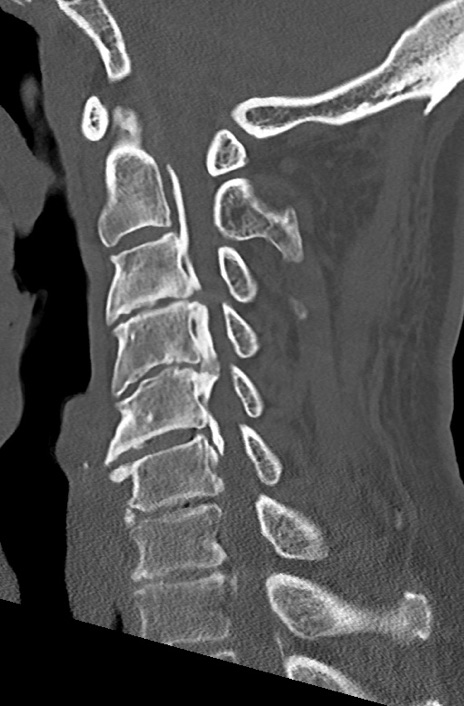

【整形】TIPS症例7 頚椎CT(矢状断像)

頚椎CT

矢状断像と横断像